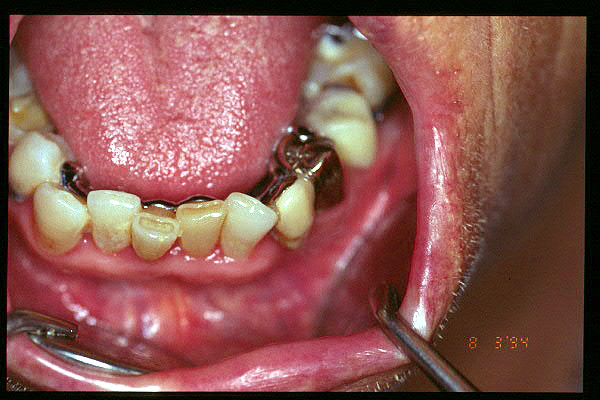

CM Esquelético superior